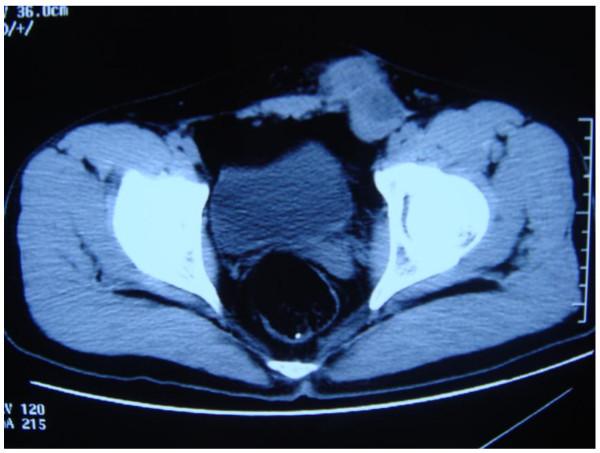

Transverse testicular ectopia (TTE) is a rare anomaly in which both testes descend through a single inguinal canal. We report a case of yolk sac tumor in the ectopic testis of a patient with TTE. A 24-year-old man presented to our hospital with a left inguinal-mass, right cryptorchidism and elevated alpha-fetoprotein (AFP). A left herniotomy 3 years earlier demonstrated both testes in the left scrotum, one above another positionally. Four months ago, a left scrotal mass appeared and radical orchiectomy of both testes revealed testicular yolk sac tumor of the ectopic testis. An enlarging left inguinal-mass appeared 2 months ago and he was referred to our hospital. Laboratory data showed an elevation of AFP (245.5 ng/ml) and a 46 XY karyotype. He underwent bilateral retroperitoneal lymph node dissection and simultaneous left inguinal mass dissection. Histopathologic examination revealed a diagnosis of recurrent yolk sac tumor in the left inguinal mass. The retroperitoneal lymph node was not enlarged and, on histopathology, was not involved. The patient has now been followed up for 8 months without evidence of biochemical or radiological recurrence.

睾丸横过异位(TTE)是一种罕见的异常情况,其中双侧睾丸通过单个腹股沟管下降。我们报告了一例 TTE 患者异位睾丸内卵黄囊瘤的病例。一名 24 岁男性因左侧腹股沟肿块、右侧隐睾和甲胎蛋白(AFP)升高来我院就诊。3 年前行左侧疝修补术,显示双侧睾丸均位于左侧阴囊,位置上下排列。4 个月前,左侧阴囊出现肿块,双侧睾丸根治性切除术显示异位睾丸的睾丸卵黄囊瘤。2 个月前出现左侧腹股沟肿块增大,并转至我院。实验室数据显示 AFP(245.5ng/ml)升高和 46 XY 核型。他接受了双侧腹膜后淋巴结清扫术和同时进行的左侧腹股沟肿块切除术。组织病理学检查提示左侧腹股沟肿块中复发性卵黄囊瘤的诊断。腹膜后淋巴结未肿大,组织病理学检查未受累。目前,患者已随访 8 个月,无生化或影像学复发的证据。